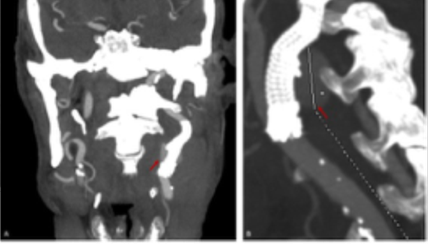

The patient was immediately taken to the operating room, where airway protection was achieved through orotracheal intubation, and the bleeding was controlled through pseudoaneurysm exclusion with a stent graft, Figure 2. Carotid artery access was achieved through a transcervical surgical approach with a suprasternal transverse incision, and an 8Fr sheath was placed in the common carotid artery (CCA). Angiography revealed the rupture in the proximal ICA, Figure 2A. The ICA was catheterized with a .035” hydrophilic guidewire, and a 7x50 mm self-expandable stent graft (Viabahn®) was deployed, with immediate resolution of the mass pulsatility, Figure 2B and 2C.

extravasating contrast from the ruptured site at the origin of the internal carotid artery; B) completion angiogram after exclusion with a self-expandable stentgraft; C) 7x50 mm Viabahn® deployed from the origin of the internal carotid artery.